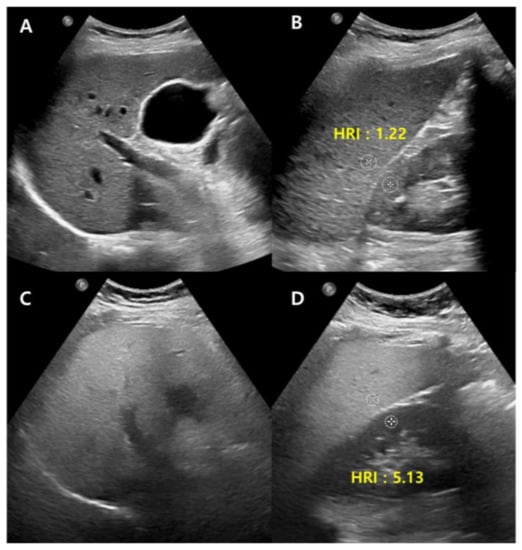

Conventional US carry disadvantages that are mostly due to inter-observer bias, though the technique can be made more objective in many ways, most straightforwardly, by normalizing the signal to the cortex of a healthy kidney. The liver-to-kidney ratio (hepatorenal index) (Figure 2) can be used to improve the technique and it has been useful in detecting liver steatosis [22,23]. However, the hepatorenal index has limitations in some patients as a result of the comorbid existence of kidney disease and anatomical variations, and it has been shown to struggle between differentiating absent and mild steatosis [24].

Figure 2.

Conventional US of a healthy liver (A) and severe hepatic steatosis (C) with hepatorenal index (HRI) (B,D). Normal hepatic parenchyma echogenicity shows well-visible intrahepatic structures such as the portal vein, hepatic vein, and liver parenchyma (A). The HRI measures 1.22 (35.1/28.8, normal < 1.5) in a healthy liver (B). Severe hepatic steatosis shows poorly visible portal vein wall echo and hepatic vein (C), and the HRI measures 5.13 (66.8/13.0) (D).